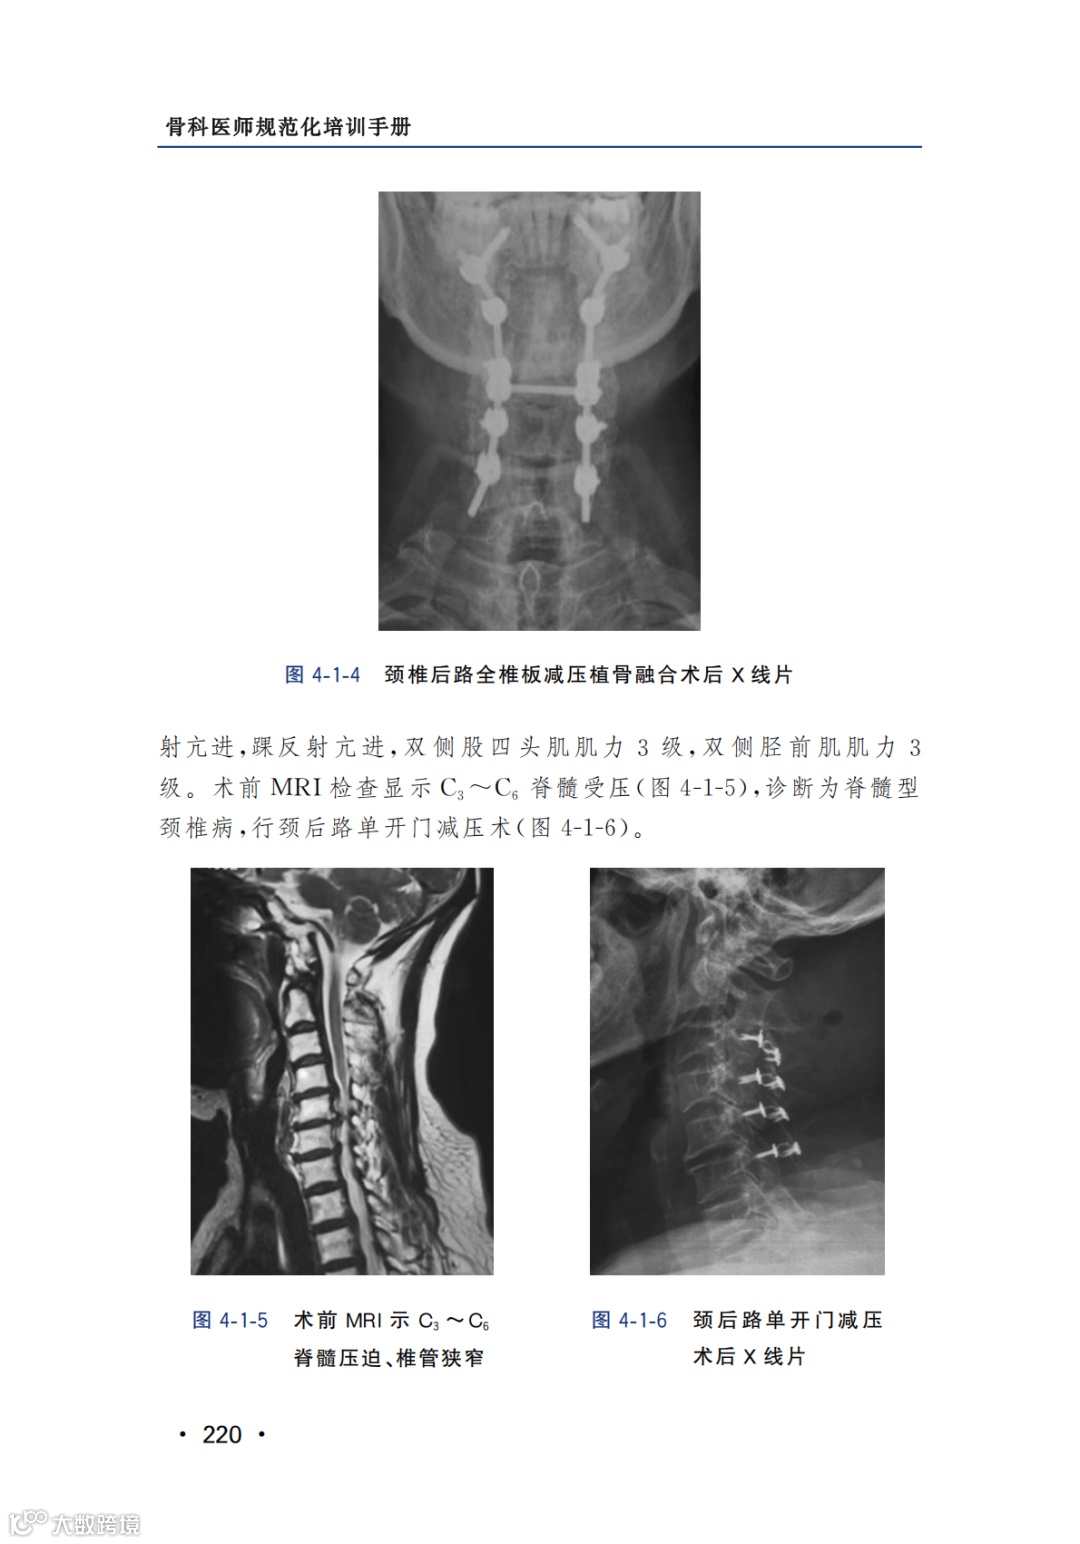

内容节选